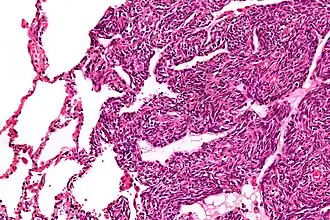

![]() Micrografía de un sarcoma sinovial monofásico. El aspecto histológico es inespecífico y se superpone con MPNST y fibrosarcoma. Tinción H&E. | ||

Dos tipos de células pueden verse microscópicamente en el sarcoma sinovial. Un tipo fibroso, conocido como huso o célula sarcomatosa, es relativamente pequeño y uniforme, y se encuentra en láminas. El otro es epitelial en apariencia. El sarcoma sinovial clásico tiene una apariencia bifásica con ambos tipos presentes. El sarcoma sinovial también puede parecer poco diferenciado o ser fibroso monofásico, que consiste solo en láminas de células fusiformes. Algunas autoridades[8] afirman que, muy raramente, puede haber una forma epitelial monofásica que causa dificultad en el diagnóstico diferencial. Dependiendo del sitio, existe una similitud con el sarcoma sinonasal bifenotípico, aunque los hallazgos genéticos son distintivos.